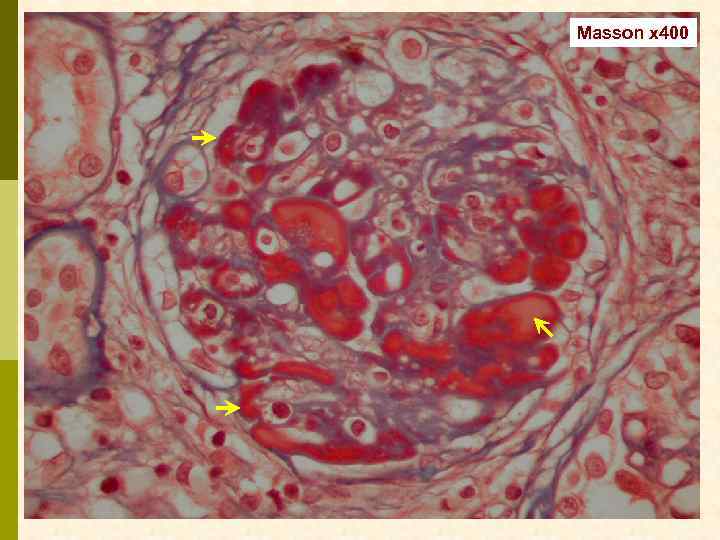

Masson x 400

Masson x 400

Предварительное гистологическое заключение: p Мембрано-пролиферативный, HCV-ассоциированный, криоглобулинемический(? ) гломерулонефрит с полным склерозом 47% клубочков, сегментарным склерозом 22% клубочков и формированием полулуний в 15% клубочков; p диффузно-очаговый выраженный острый канальцевый некроз; p выраженный артерио-артериолосклероз. Примечание: Криоглобулинемическая природа поражения будет уточняться при ЭМ-исследовании.

Заключение p Мембрано-пролиферативный гломерулонефрит, криоглобулинемический, ВИЧ-ассоциированный, на фоне гепатита С